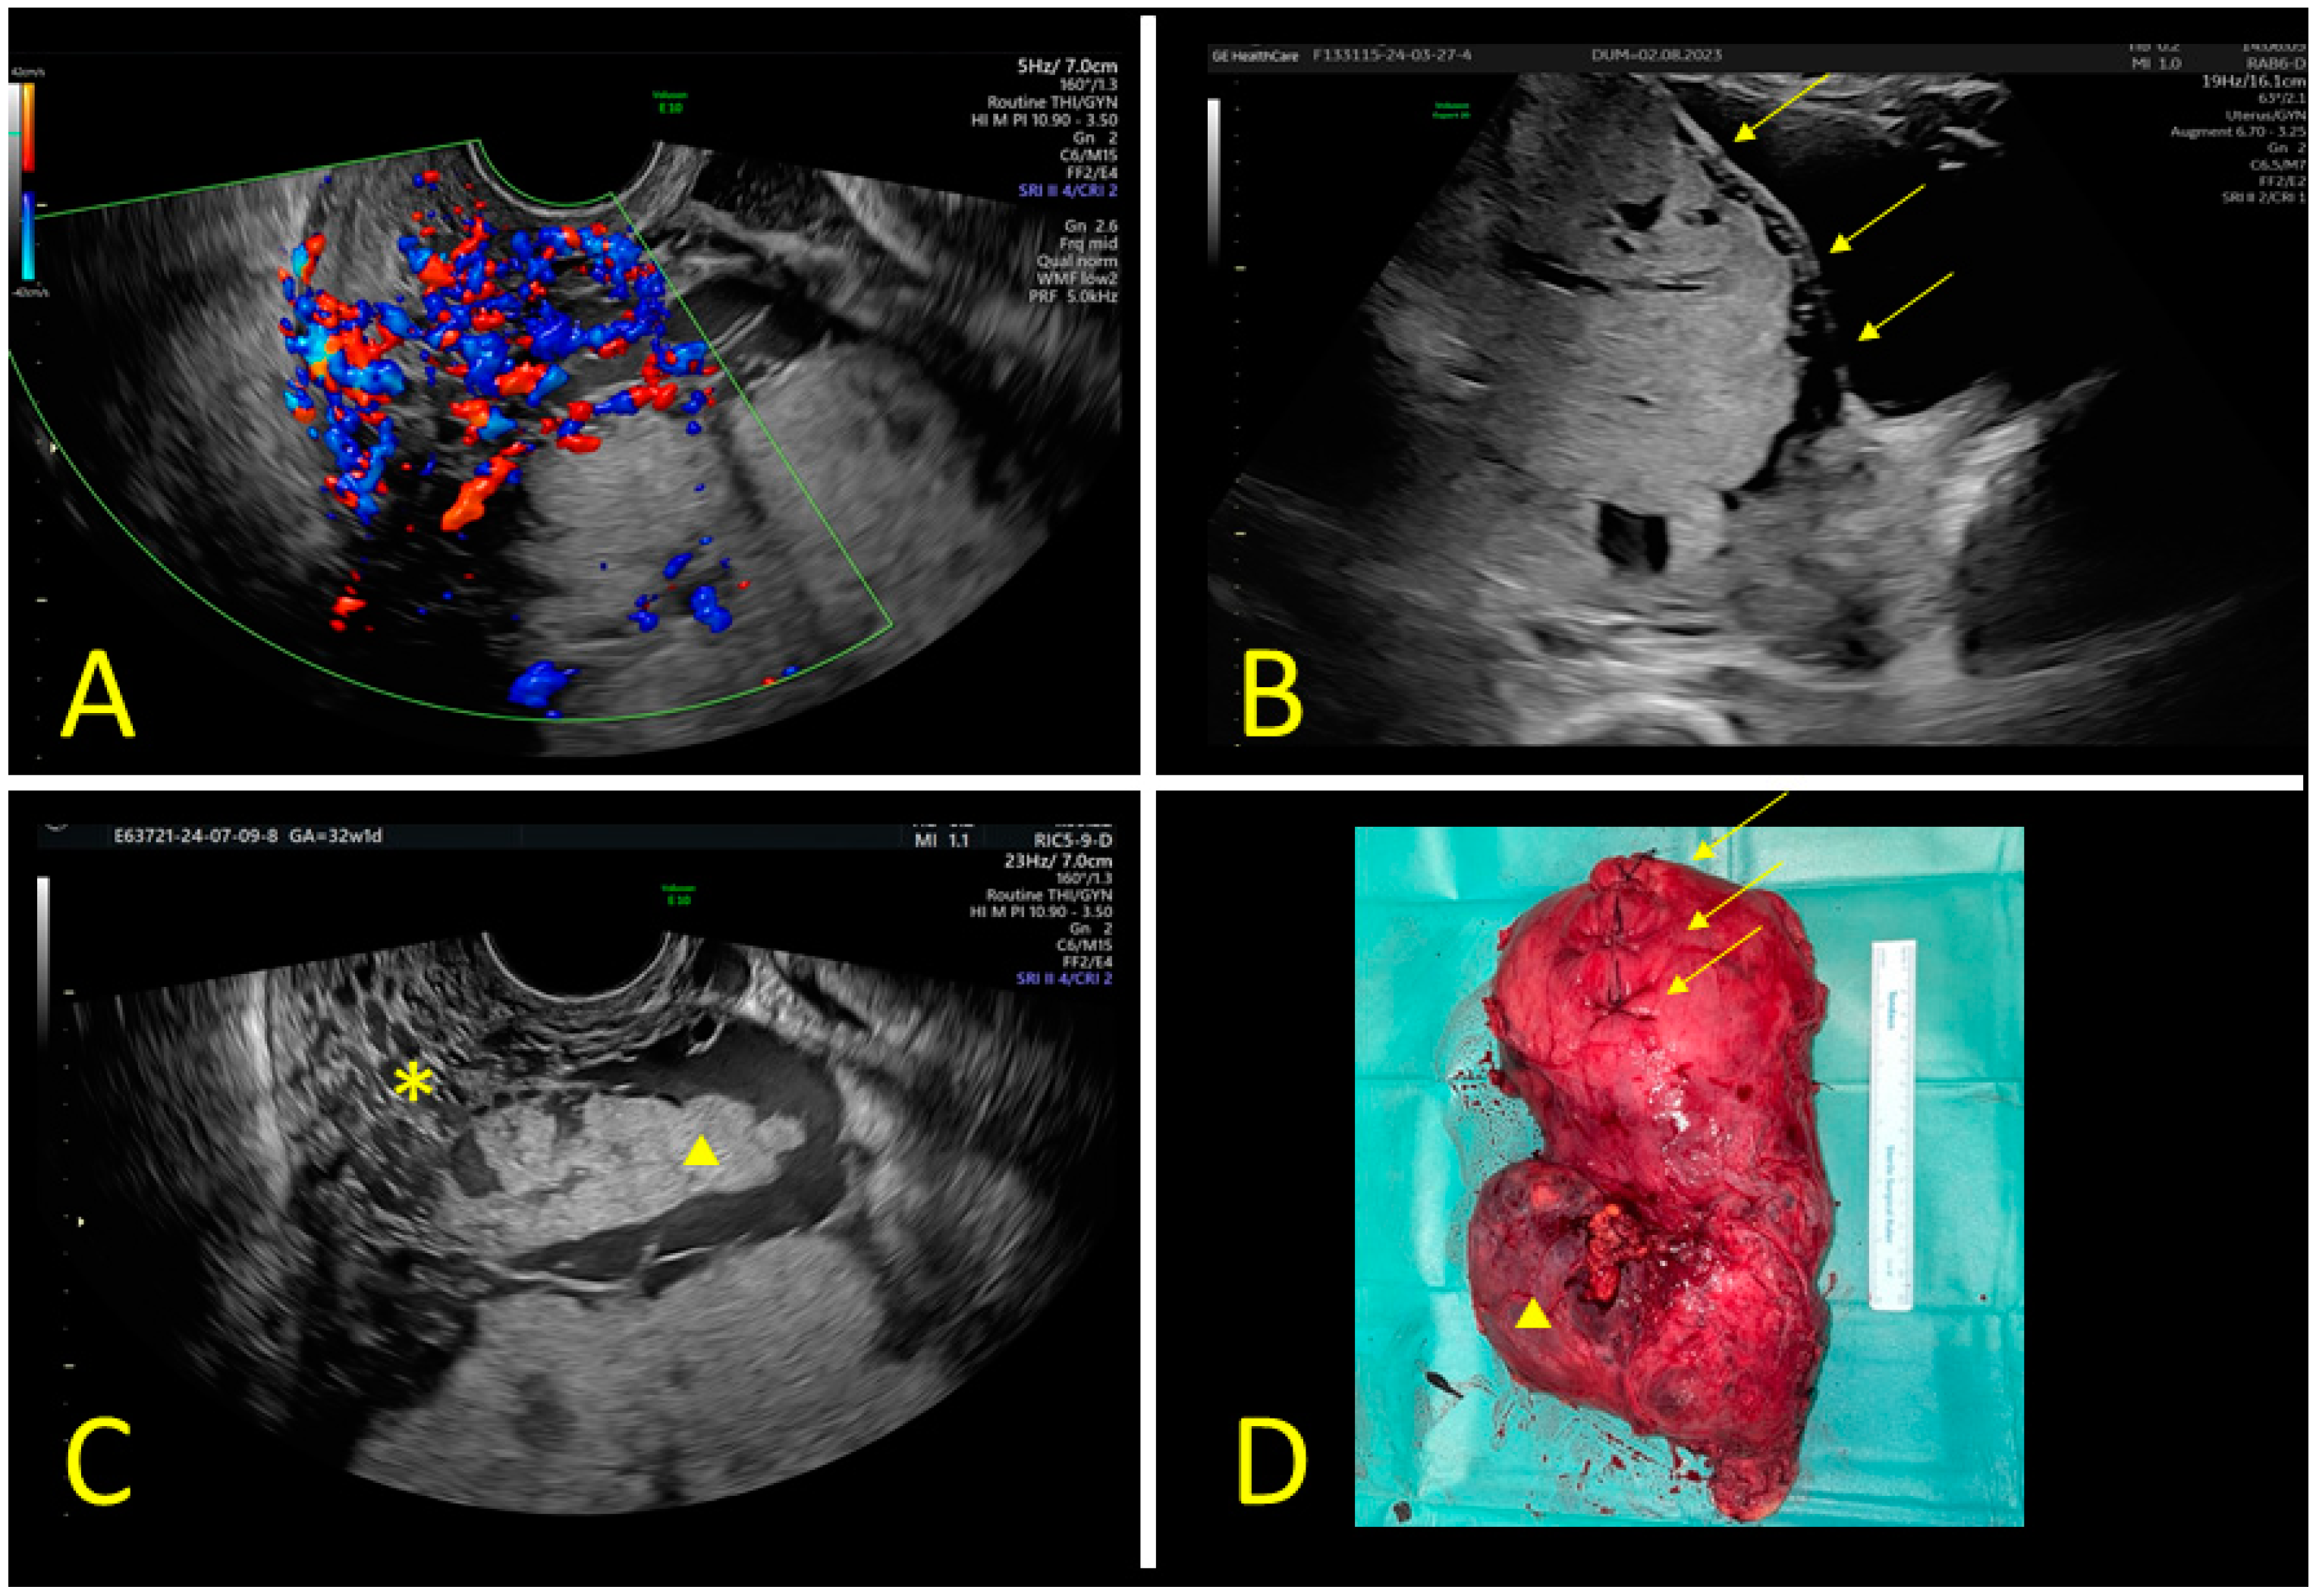

- Vimercati, A.; Galante, A.; Cirignaco, F.; Nicolì, P.; Malvasi, A.; Cicinelli, E.; Cerbone, M. The sonographic assessment to diagnose Placenta Accreta Spectrum disorders: “Riddled Cervix” and other signs. Arch. Gynecol. Obstet. 2024, 310, 1265–1266. [Google Scholar] [CrossRef] [PubMed]